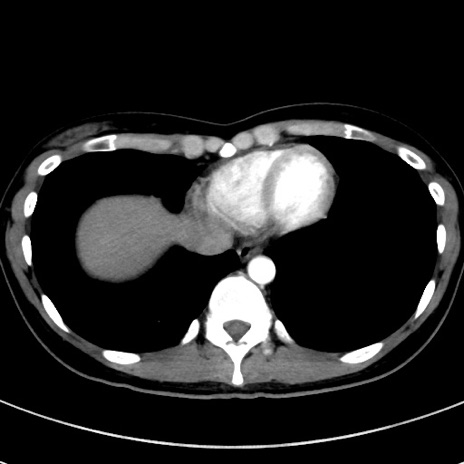

冠状断像

【症例】20歳代女性

【主訴】嘔吐、下腹部痛

【現病歴】昨日夕食後に嘔吐し下腹部痛が出現。本日になっても嘔吐持続し改善しないため来院。

【身体所見】意識清明、BT 37.2℃、BP 108/67mmHg、腹部:平坦、やや硬、下腹部正中から右にかけて圧痛あり、反跳痛軽度あり、tapping pain(+)。

【データ】WBC 13600、CRP 14.94